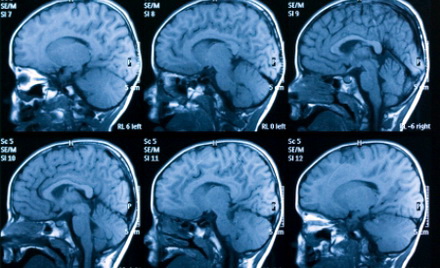

Pentru studiu au fost comparate rezultatele în urma scanării creierului a 17

bărbaţi şi femei, cu vârste cuprinse între 14 şi 21 ani, care trăiesc în China,

care au fost diagnosticaţi cu dependenţă de Internet cu rezultatele testărilor

unor oameni care nu prezintă niciun fel de afecţiune.

Cercetătorii au descoperit mai multe "anomalii ale materiei albe" în

timpul scanării creierelor celor depedenţi de Internet. Rezultatele indică

faptul că traseele neuronale ale celor testaţi au întreruperi pe rutele legate

de emoţii, luarea deciziilor şi auto-controlul.

Comparând cu rezultatele unor testări mai vechi, aceleaşi anomalităţi au fost

descoperite şi în cadrul tomografiilor persoanelor dependente de alcool,

cocaina, heroină, marijuana sau ketamină.